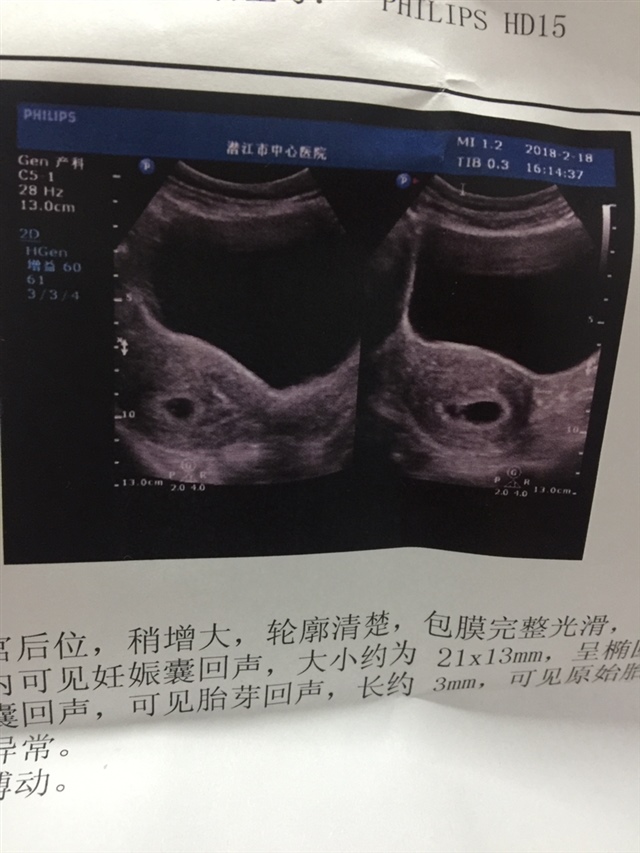

Dong Lian[帖主]:什么意思啊亲?看不出来吗现在。